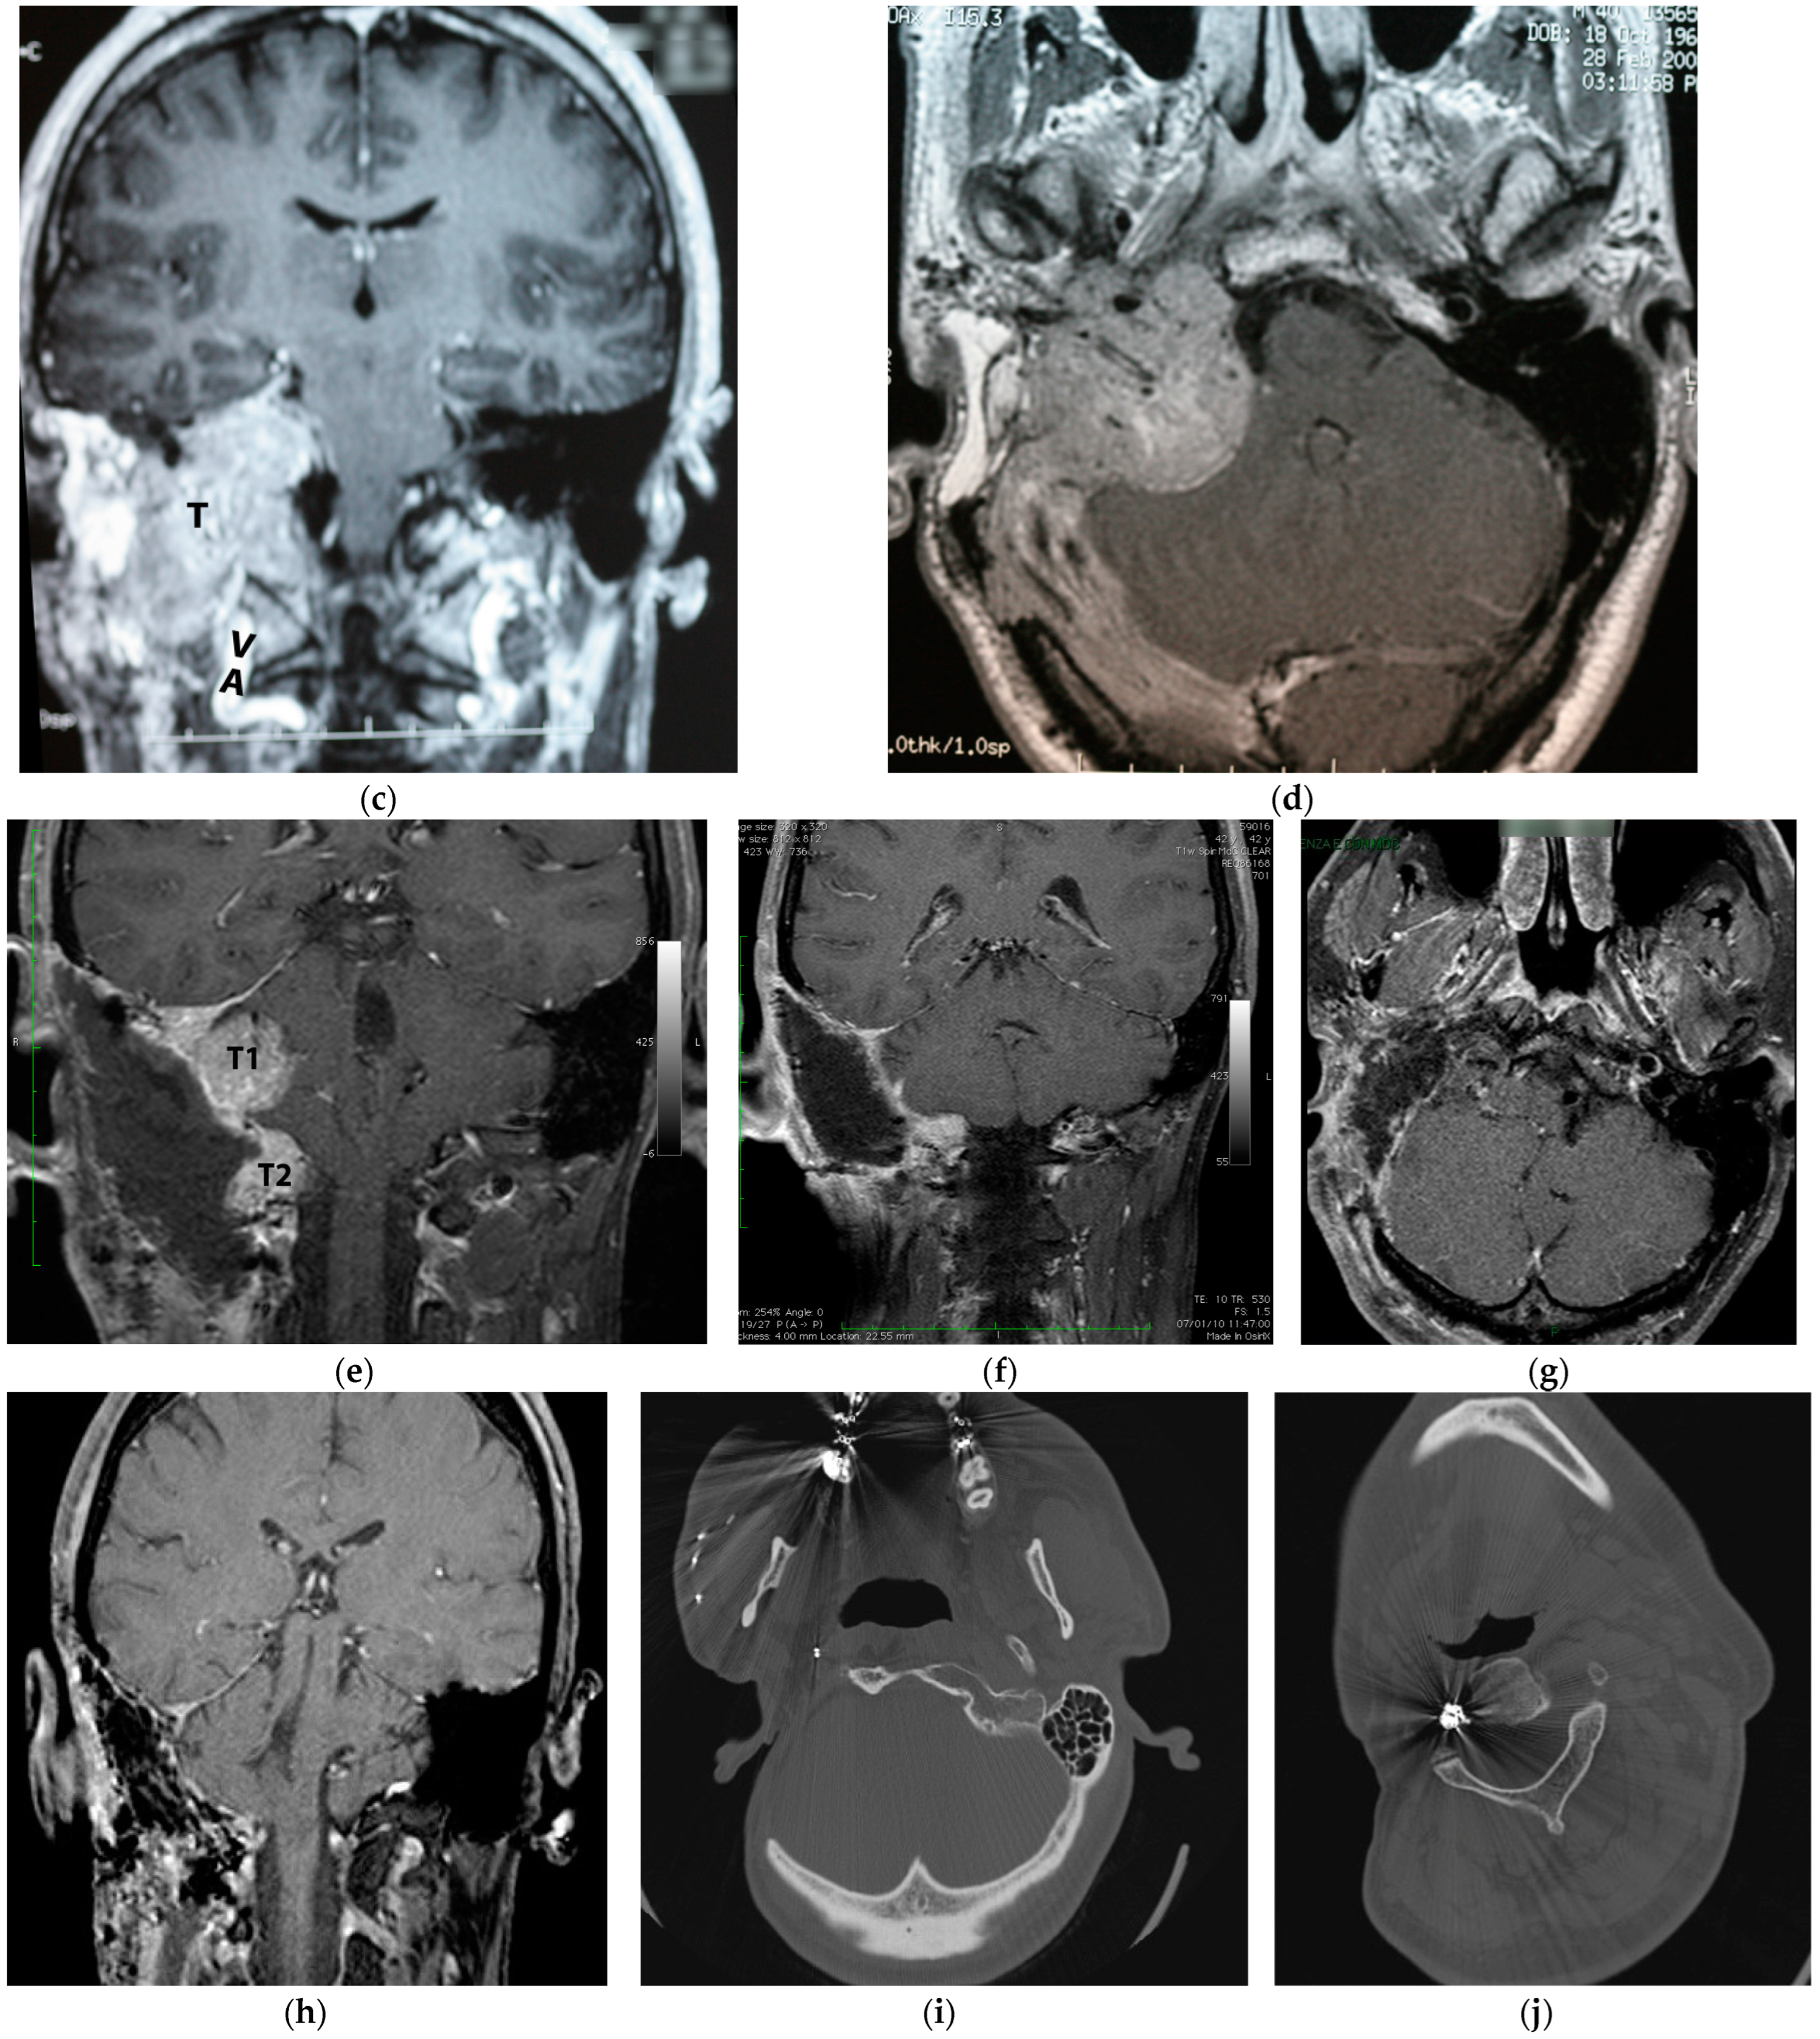

5.2. Case 2: (C3Di1 + Stage I VP)

5.3. Case 3: (C4Di2Vi)

5.4. Case 4: (C3Di2 + Stage II Vagal PGL)

5.5. Case 5: (C3Di2Vi)

5.6. Case 6: (C4Di2Vi)